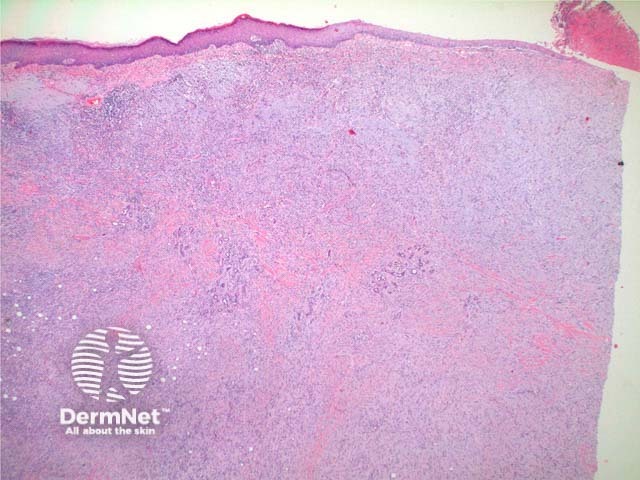

Scanning power view of histology of leiomyosarcoma shows a poorly circumscribed tumour nodule which may be dermal based in the less common dermal leiomyosarcoma (Figure 1) or deeply infiltrating in the subcutaneous form. The tumour is comprised of a spindle cell proliferation forming rough bundles and fascicles (Figures 2 and 3). High power demonstrates spindle cells with cigar shaped nuclei with prominent cytologic atypia and mitotic figures (Figures 4 and 5).

Figure 1